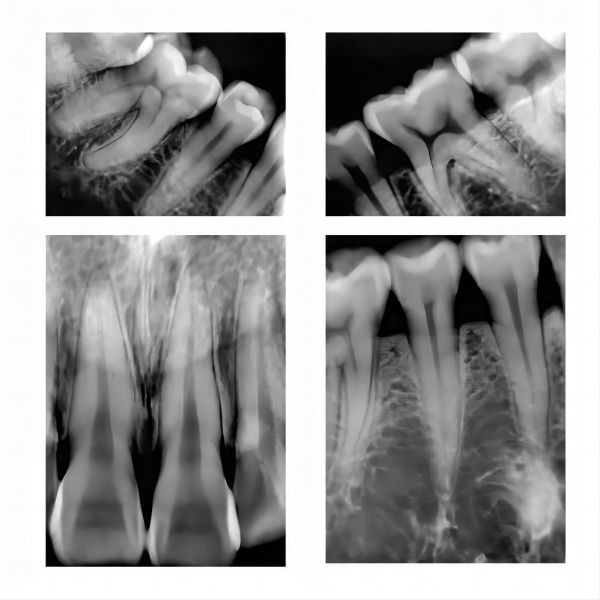

Imported ball tube shoot film ultra clear

Lightweight Dental X Ray Device Sensor Camera Digital X Ray Equipment Images |